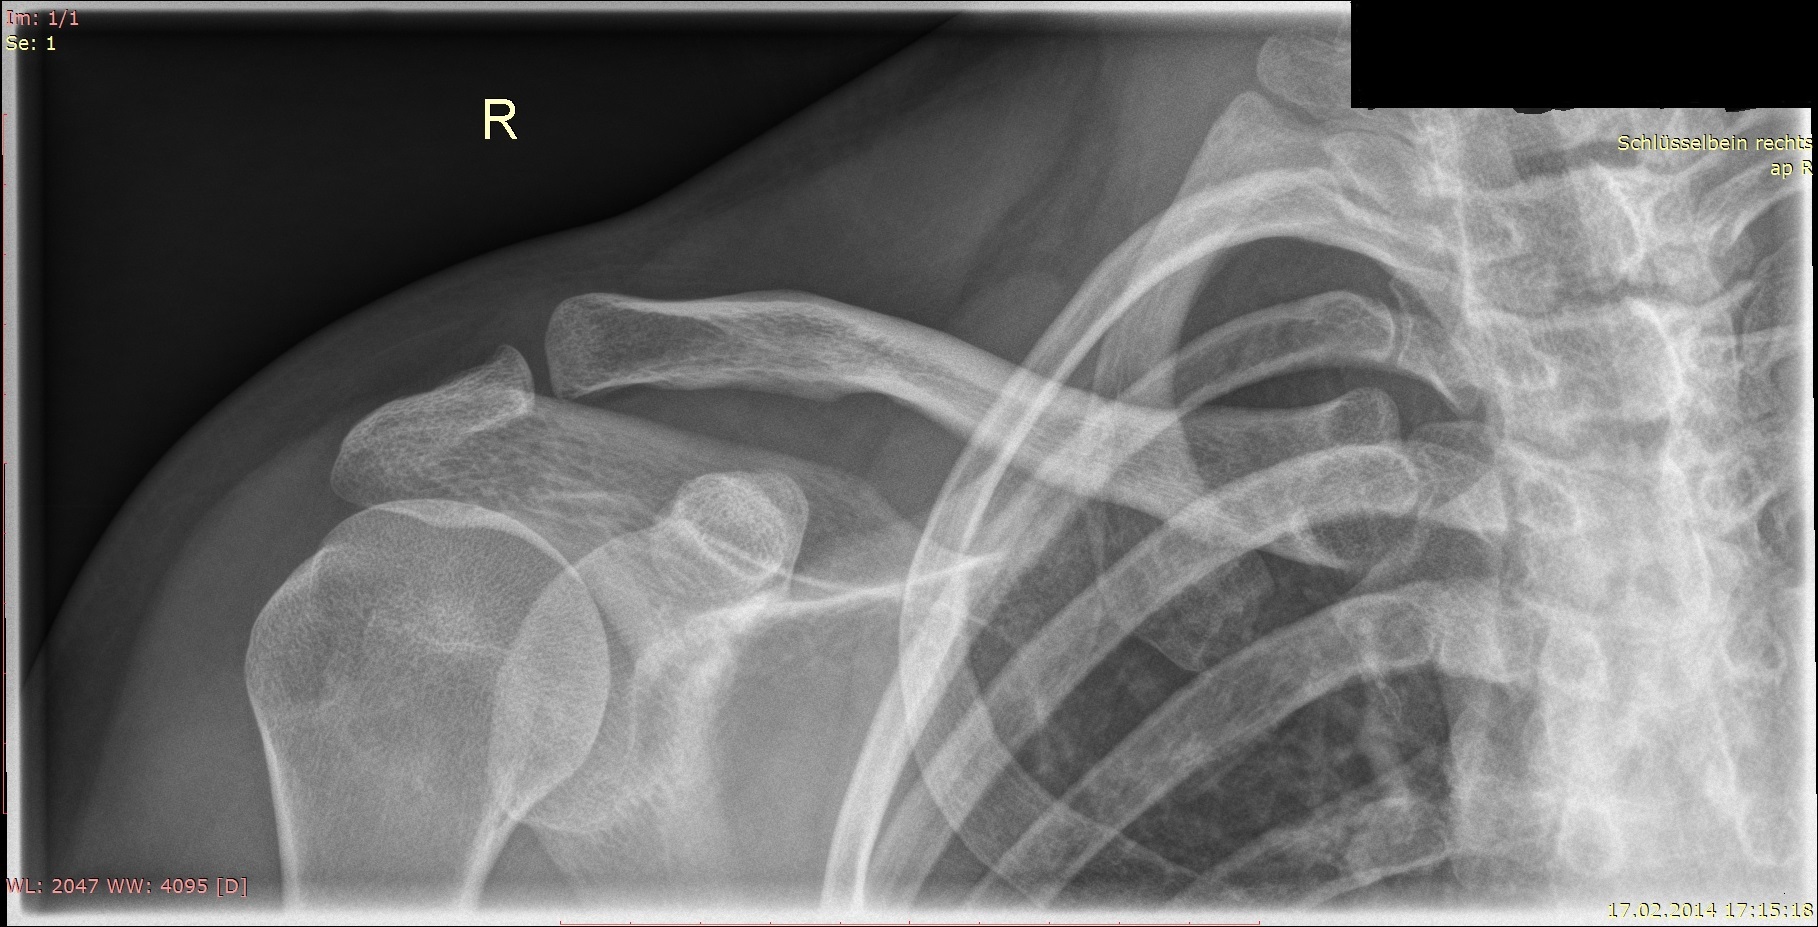

Schlüsselbeinbruch » Ursachen, Symptome & Behandlung

Schmerzen am Schlüsselbein einseitig Ursachen, Diagnose und effektive Behandlung

Die Schwellung, meist am oberen Rand des Brustbeins, wird Tietze Syndrom genannt. Es handelt sich um eine Entzündung des Rippen / Brustbeingelenks und ist deshalb leicht seitlich des Brustbeins zu finden. Häufig ist die erste Rippe betroffen, da hier zusätzlich zur Rippe auch das Schlüsselbein mit dem Brustbein verbunden ist.. Was können Ursachen sein, wenn das Schlüsselbein geschwollen ist? Geschwollene Lymphknoten am Schlüsselbein. Tietze Syndrom. Verletzungen des Knochens (Schlüsselbeinfraktur) Degeneration (Arthrose an den Schlüsselbeingelenken) Verletzung des Muskels (Muskelfaserrisses der Brust) Überlastung. Fehlbelastung. Schlüsselbeinbruch.